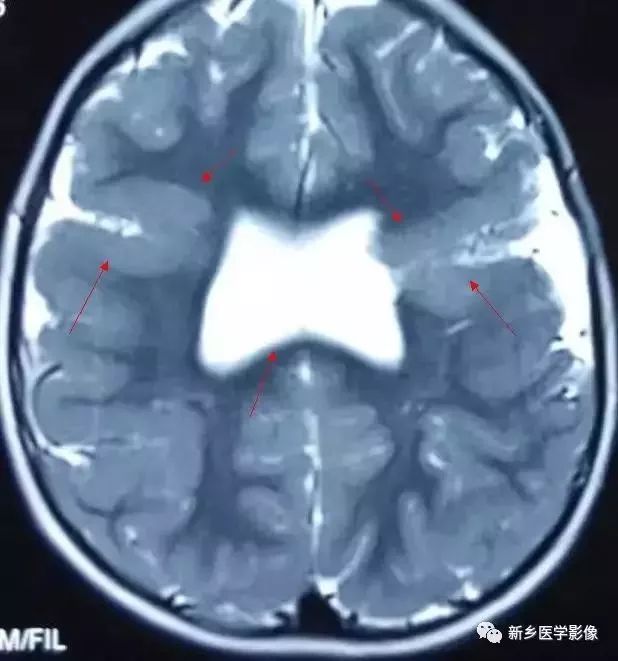

脑裂畸形:

脑裂畸形发生在胚胎期神经元移行阶段。脑裂畸形可累及一侧或双侧大脑半球。脑裂畸形位于侧面,常累及中央前、后回区,偶尔位于大脑半球的其他部位。

脑裂畸形的裂隙可以很窄,裂隙两侧灰质紧密相贴,称闭合型;裂隙也可以很宽,中间为脑脊液,称分离型。

临床上脑裂畸形常表现有癫痫发作,其他神经系统症状可从很轻微到很严重.主要取决于脑裂畸形使脑组织缺损的严重程度。单侧闭合型脑裂畸形症状通常较轻,双侧分离型脑裂畸形症状较明显。